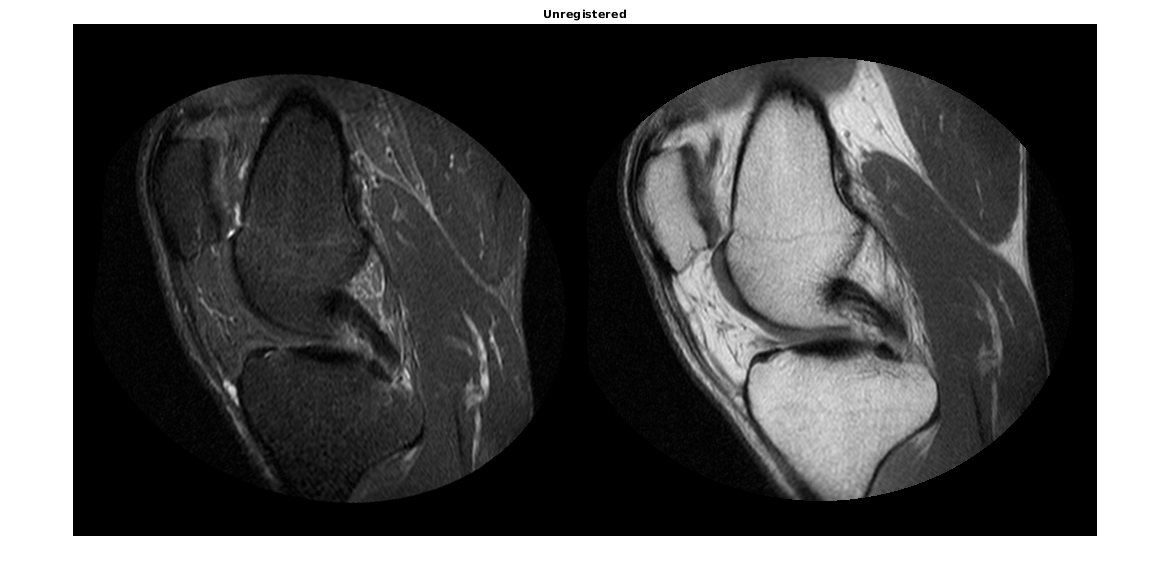

Этот пример использует два изображения MRI колена. Фиксированное изображение является двойным изображением вращения, в то время как движущееся изображение является двойным изображением вращения с восстановлением инверсии. Два стреловидных среза были получены одновременно, но немного неровно.

Функция imshowpair полезна, чтобы визуализировать изображения во время каждой части процесса регистрации. Используйте его, чтобы видеть два изображения индивидуально способом монтажа или отобразить их сложенный, чтобы показать объем неверной регистрации.

imshowpair(moving,fixed,'montage') title('Unregistered')

В перекрывающемся изображении от imshowpair серые области соответствуют областям, которые имеют подобную интенсивность, в то время как пурпурные и зеленые зоны показывают места, где одно изображение более ярко, чем другой. В некоторых парах изображений зеленые и пурпурные области не всегда указывают на неверную регистрацию, но в этом примере это просто в использовании информация о цвете, чтобы видеть, где они делают.